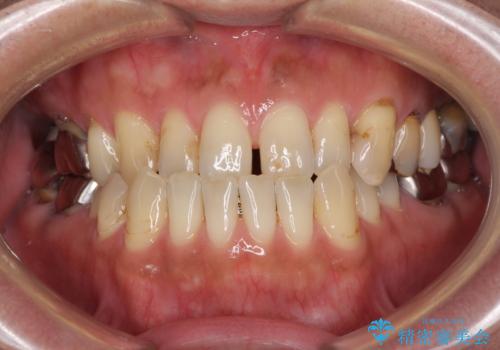

前歯の反対咬合をワイヤー矯正で改善して噛みやすく

- 咬み合わせの悪さを気にして来院された患者様です。

来院当初は、奥歯の銀歯が問題で咬み合わせが悪いと思っていらっしゃいましたが、前歯の反対咬合を改善することが最優先とご説明し、矯正治療を行うこととしました。